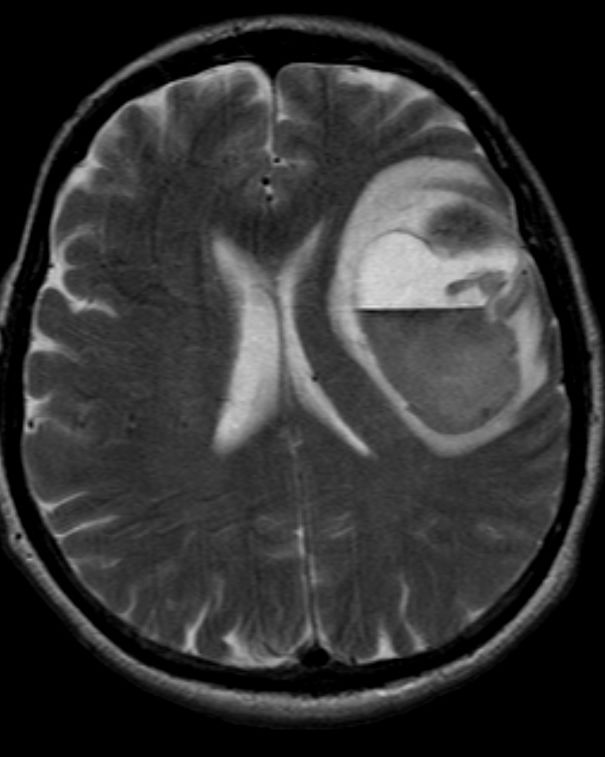

Antonio è vittima di un tumore molto aggressivo: originario da un polmone si è succissivamente diffuso creando metastasi al cervello. Anni di terapia sembrano non fare effetto e Antonio si sente -giustamente- scoraggiato.

Finalmente, sembra aver trovato la tanta agognata cura: una particolare dieta vegana. Antonio, un po’ per disperazione, un po’ perché spinto dalla famiglia, decide di provare la dieta. Per sicurezza, sceglie di contattare la dottoressa Michela de Petris, medico nutrizionista all’Ospedale San Raffaele di Milano, che gli “prescrive” la sopracitata dieta. In pochi mesi, Antonio sembra guarire del tutto, la metastasi è scomparsa ed è più in forma che mai. Che questa dieta sia la cura definitiva per il cancro?